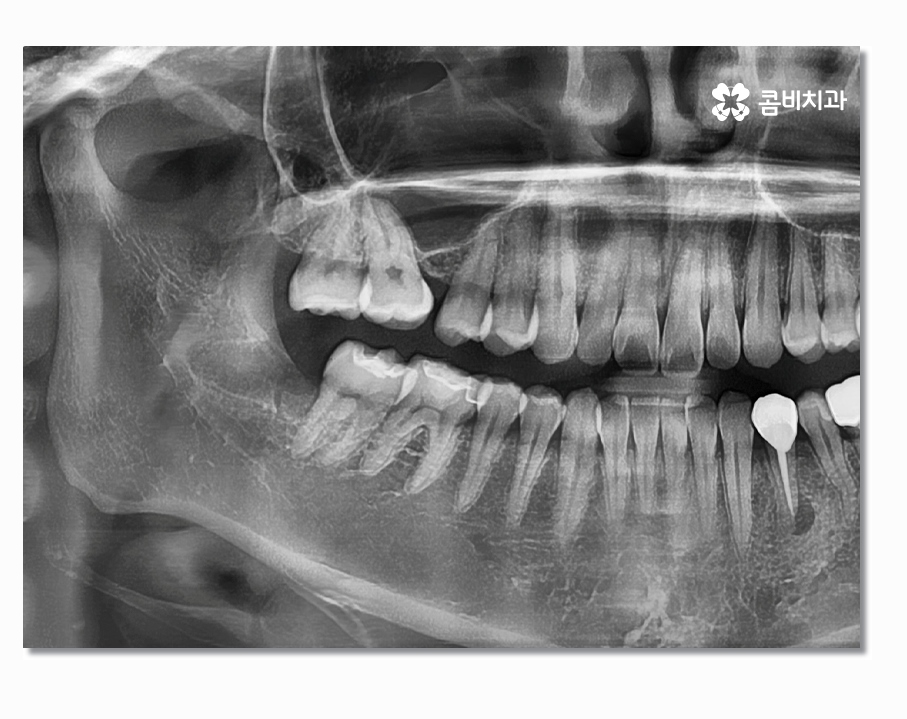

보시는 것처럼 부분매복사랑니의 경우 음식물이 끼기 쉽고

치석이 쌓이기 쉽지만 칫솔질은 어렵기 때문에

충치가 발생하여 어금니까지 함께 손상되거나

특히 잇몸질환이 발생하는 경우가 많다고 할 수 있는데요

부분매복사랑니의 경우 치아가 반쯤만 잇몸 위에 맹출 되어 있어서

충치 및 잇몸질환을 일으키기도 하지만 누워서 자라는 형태인

경우도 많은데 이경우 어금니 사이에 충치를 발생시키거나

어금니를 녹게 만드는 경우도 있기 때문에 어금니 손상을 방지하기

위해서라도 발치를 서둘러야 하는 경우가 있어요

사랑니는 겉으로 보이는 것과 X Ray로 살펴보는 것이

큰 차이가 있으며 사랑니의 위치와 맹출 형태, 크기 등에 따라서

발치의 과정부터 시술 난이도의 차이가 있기 때문에